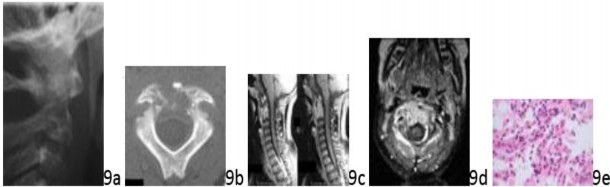

Question 9 A 7-year-old boy has a 3-week history of neck pain. History and physical examination reveal no neurologic symptoms. A radiograph, CT scan, and MRI scans are seen in Figures 9a through 9d. Figure 9e shows a needle biopsy specimen. Based on these findings, what is the most appropriate management?

Question 9 A 7-year-old boy has a 3-week history of neck pain. History and physical examination reveal no neurologic symptoms. A radiograph, CT scan, and MRI scans are seen in Figures 9a through 9d. Figure 9e shows a needle biopsy specimen. Based on these findings, what is the most appropriate management?

1. ## Cervical collar and observation

2. ## Intravenous antibiotics and cervical collar

3. ## Chemotherapy and radiation therapy

4. ## Neoadjuvant chemotherapy alone

5. ## Neoadjuvant chemotherapy and surgical resection

DISCUSSION: The findings are consistent with eosinophilic granuloma. Eosinophilic granuloma is a focal destructive lesion of bone commonly seen in children younger than age 10 years. Despite the very aggressive appearance of these lesions, they

typically will heal spontaneously or following biopsy. Local corticosteroid injection has been advocated by some. Surgical decompression is indicated in rare cases of cord compression. Chemotherapy is indicated only in disseminated forms of histiocytosis. The Preferred Response to Question # 9 is 1.